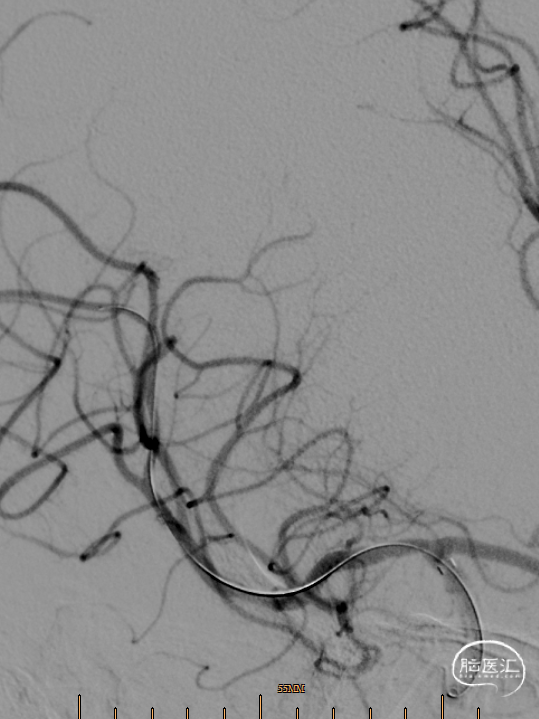

诊疗经过